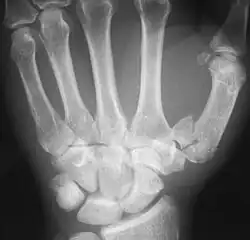

The Rolando fracture is a type of broken finger involving the base of the thumb.[1]

It is an intra-articular fracture.[2]

It was first described in 1910 by Silvio Rolando.[3] It is typically T- or Y-shaped.[4]